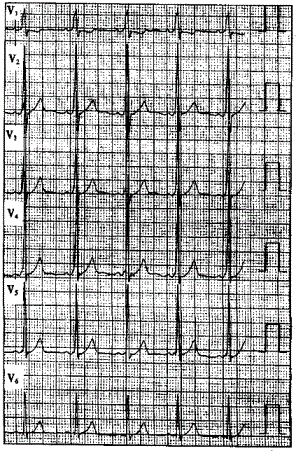

问题 患者男性,40岁,多次发作心悸,心电图一-见下图,显示为预激图形。 ? ? 食管电生理检查测得旁路前传有效不应期为240ms,提示

选项 A.低危旁路 B.高危旁路 C.非危险旁路 D.可能危险 E.以上都不是

答案 B

解析 :食管心房调搏可以诱发心动过速并确定心动过速的发生机制该心电图显示V导联delta波向上,旁路位于左侧;Ⅱ、Ⅲ、aVF导联delta波向上,提示旁路位于左侧壁;当旁路前传有效不应期<270ms或预激综合征合并心房颤动时最短RR间距≤240ms时,提示为高危旁路;逆向型房室折返性心动过速的折返途径为:心房→旁路→心室→房室结→心房